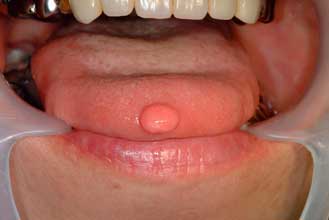

○ 非歯原性良性腫瘍:一般的な症状としては無痛性に周囲組織を圧排あるいは外向性に緩慢に増大

し、腫瘍が相当に大きくなるまでは機能障害もありません。腫瘍の種類として多いものは乳頭腫、

線維腫です。次に多いものは血管腫です。その他化骨性線維腫、リンパ管腫、脂肪腫などがありま

す。治療としては外科的切除が基本です。血管腫では薬剤を用いた硬化療法を行うこともあります。

| 舌線維腫 | 舌血管腫 | |